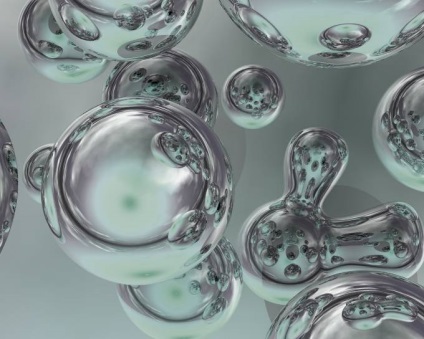

Fotó: Ásványi olajok

A legjobb eredményeket, hidratáló a gyermekek és felnőttek dermatitis, azt mutatják, hasznosítására képlet: vízmolekula körül molekulák a készítmény az olaj.